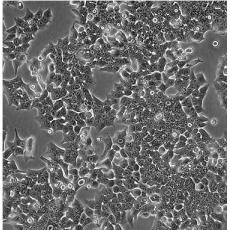

HCT 116

中文名稱 人結直腸腺癌細胞

組織來源 結腸腺癌;男性

生長特性 adherent

形態特征 epithelial

細胞描述 The cells are positive for keratin by immunoperoxidase staining.HCT 116 cells are positive for transforming growth factor beta 1(TGF beta 1) and beta 2(TGF beta 2) expression.